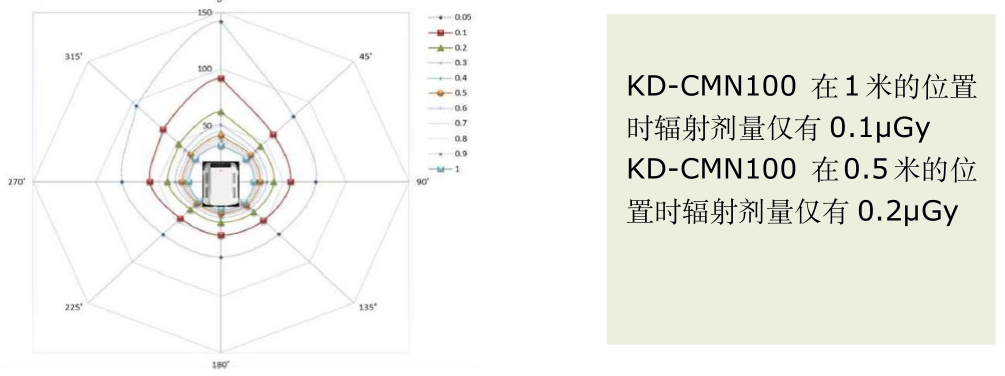

优化安全的低剂量辐射管控

微米级焦点球管设计及低剂量曝光控制,使得产品整机的漏辐射保持在较低的水平。 据国家漏辐射检测标准可知,在加载状态下的漏辐射应不超过 1.0mGy/h,而非加载状态下的漏辐射应不超过 20μGy/h。 CMN100 关于该项的检测结果为加载状态下不高于 0.41mGy/h,非加载状态下为 0μGy/h。

关于我们 MINIC 散射线辐射剂量的问题,可以拿机场和高铁站安检的设备对比。 根据国家标准 GB 15208.1-2005 规定,X 光安检仪的单次检查剂量不应大于 5µGy,同时在距离设备外表面 5cm 的任意处(包括设备入口、出口处)X 射线剂量应小于5µGy/h[2], 此标准与美国 FDA 的标准相同。实际上,在地铁和机场中所使用的 X 光安检仪的辐射剂量,比国家标准规定的还要低上许多。